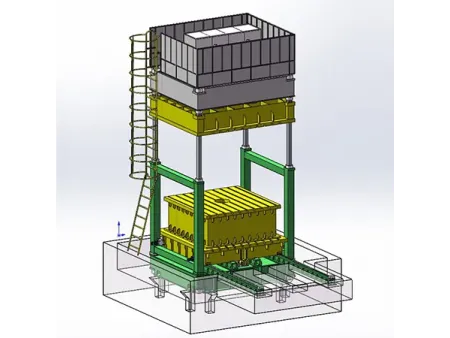

Arco en C con Intensificador de Imagen

Gracias a su intensificador de imagen, este equipo de imagenología ofrece una visualización estable y de la mejor calidad, mientras reduce al mínimo la exposición a la radiación. Incorpora un generador de alto voltaje y tecnología de alta frecuencia que garantizan un rendimiento confiable incluso en los entornos quirúrgicos más exigentes. Su pantalla táctil LCD de 10.4 pulgadas es intuitiva, gira hasta 180° y está fabricada con materiales resistentes a la corrosión. Además, incluye un sistema de mensajes de error en chino lo que facilita la resolución de problemas para usuarios locales.

Inlcuye funciones avanzadas tales como fluoroscopía por pulsos y modo boost, para obtener imágenes claras y detalladas que permiten diagnósticos más seguros y procedimientos quirúrgicos más precisos. El diseño ergonómico incluye una manija para maniobras rápidas y una rueda con bloqueo de dirección que asegura estabilidad durante el uso. Su arco de 800 mm ofrece un amplio margen de movimiento para trabajar con mayor libertad. Además, cuenta con triple campo de imagen (9", 6", 4.5") para enfocar con precisión zonas específicas, una cámara CCD giratoria de 360° para una visión completa y rieles de guía lineal coreanos que facilitan un deslizamiento suave. Sus relés Omron contribuyen a reducir el ruido operativo y prolongan la vida útil del sistema.

Generador HF

120 kV, 5 kW, 40 kHz

- Modo fluoroscopia 40-120 kV 0,5-5 mA (kV manual y automático)

- Fluoroscopia pulsada 40-120 kV 0,5-5 mA

- Fluoroscopia boost 40-120 kV 5-10 mA

- Fotografía 40-120 kV 1-250 mAs

- Ánodo fijo de doble enfoque: 0.3 mm / 0.6 mm

- Tecnología IMD de Italia

Intensificador de imagen

Tres campos de visión 9, 6, 4.5 de Japón, marca Canon

Cámara CCD

Marca japonesa Watt, rotación de 360°

- Disminución de ruido recursiva de 5 grados

- Congelación de fotogramas

- Almacenamiento de miles de datos de imagen

- Inversión y rotación de imágenes

- Visualización en pantalla con comparación de imágenes

- Soporta impresión «one click», imprime el informe de imagen

- Equipado con puerto de red Dicom 3.0 (opcional)

- Soporta la función de exportación de datos estándar Dicom 3.0

- Recorrido vertical: 0-400 mm

- Recorrido horizontal: 0-200 mm

- Rotación alrededor del eje horizontal: ±180°

- Distancia del punto focal al generador de imágenes (SID): 1000 mm

- Profundidad en el brazo ≥ 650 mm

- Soporte móvil: 1800×800×1850 mm

- Sistema de imagen: 750×530×1680 mm

- Cámara CCD de alta resolución: 1 juego

- Generador de rayos X: 1 juego

- Intensificador de imagen de 9 pulgadas: 1 juego

- Procesador de imágenes

- Pantalla LCD de alta definición de 24'' marca Dell: 1 juego

- Soporte móvil: 1 juego

El arco en C con intensificador de imagen es una herramienta clave en distintas áreas médicas y quirúrgicas. Gracias a su versatilidad, se emplea con frecuencia en quirófanos, salas de rayos X, áreas de urgencias y unidades especializadas en procedimientos vasculares e intervenciones mínimamente invasivas. Su utilidad abarca desde cirugías generales, ortopédicas y de columna, hasta intervenciones en urología, traumatología y cirugía torácica o abdominal. También es indispensable en procedimientos como la fijación de fracturas, estudios endoscópicos, angiografías discales y tratamientos vasculares como la angioplastia.